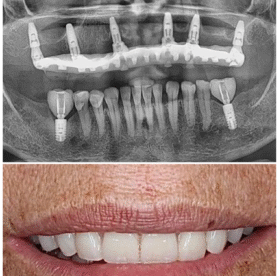

Recupera tu sonrisa y la confianza de morder, hablar y sonreír sin preocupaciones. Nuestros implantes de alta calidad ofrecen máxima durabilidad, estética natural y la seguridad de contar con garantía certificada. Una solución definitiva para reemplazar dientes perdidos y mejorar tu calidad de vida.

Restauraciones integrales que devuelven función, estética y confianza, respetando completamente tu biología natural.